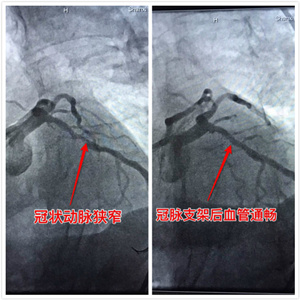

冠状动脉造影是诊断青年冠心病的“金标准”,尤其是青年冠心病患者多以急性心肌梗死起病,就诊后应急诊行冠脉造影检查。

4、对于行冠脉内支架植入术的患者,患者应遵医嘱用药、定期复查,坚决杜绝随意停药、减药。